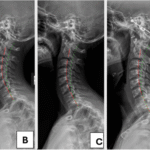

Hipolordoz ve Hiperlordoz

Boyun eğriliğinin azalması (hipo-lordoz) veya fazla artması(hiper-lordoz) sorunlarına yol açabilir. Boyundaki bu değişiklikler kötü duruş, omurga yaralanmaları veya doğuştan omurga rahatsızlıkları gibi faktörlerden kaynaklanabilir.

Servikal Lordozun Düzleşmesinin Nedenleri

Servikal lordozun düzleşmesi çeşitli nedenlerden kaynaklanır. Tipik nedenler şunlardır:

• Travma veya Yaralanma: Boyun omurgası, boynu anormal bir pozisyona iten trafik kazaları gibi yaralanmalar sonucunda düzleşebilir. Küçük yaralanmalar bile omurga hizalamasını uzun süre etkileyebilir.